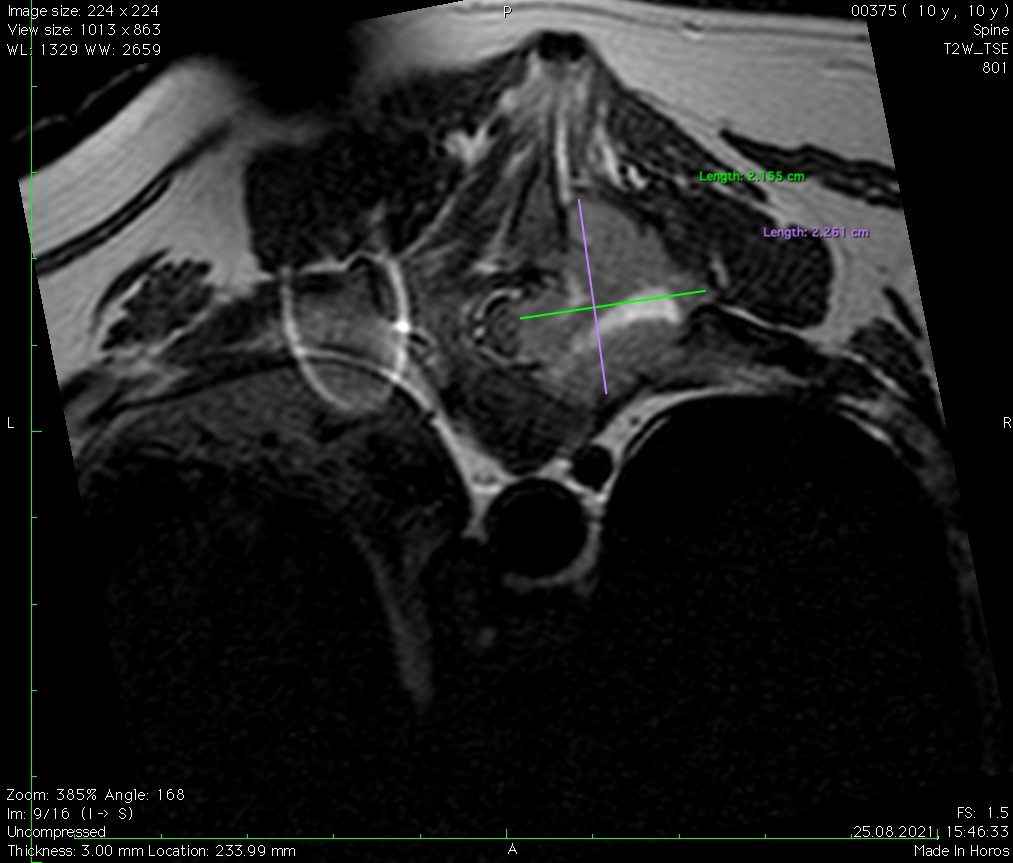

Заключение МРТ:

Признаки очагового образования с накоплением контраста в СМК на уровне Th10 (правая сторона) размером 2,2 х 2,3 см с поражением позвонка, окружающие ткани, выраженной компрессией СМ. С левой стороны на данном уровне отмечается артефакты. На уровне Th12-L2, L6-S1 отмечаются протрузии дисков.